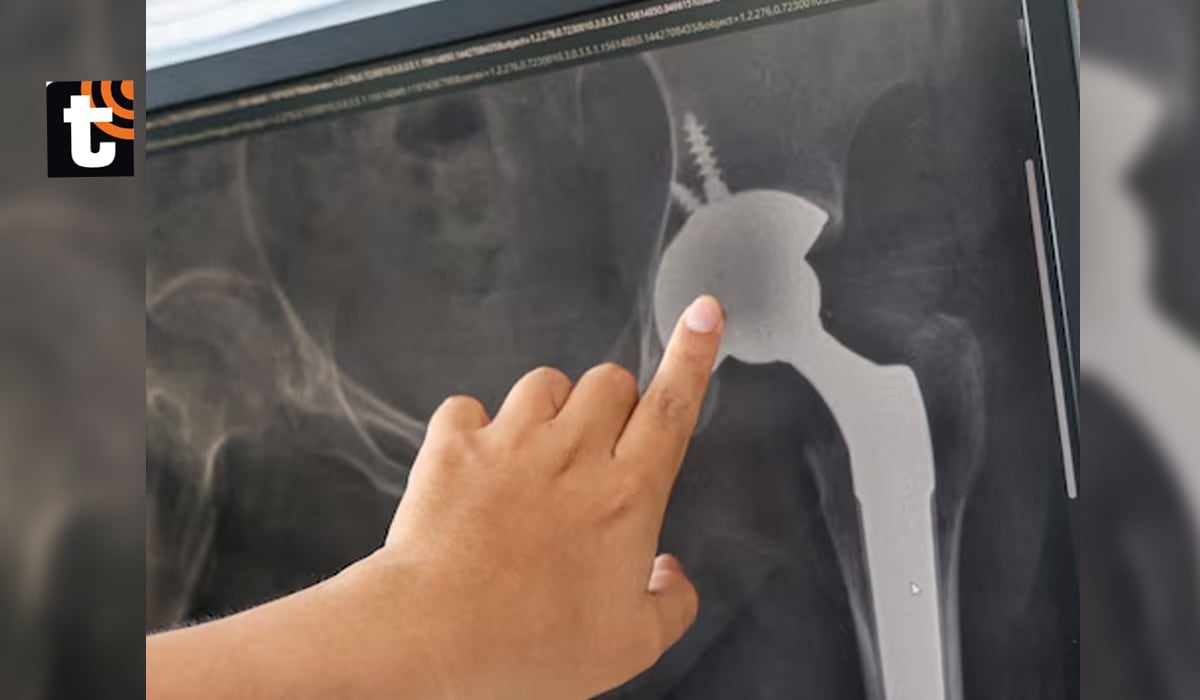

El especialista explicó que la cirugía consistió en extraer la cabeza femoral fracturada y colocar un implante avanzado. Según detalló: “Se optó por una prótesis no cementada con copa de doble movilidad, ideal para reducir el riesgo de luxación debido a antecedentes patológicos de columna del paciente”.

El hospital Rebagliati, con más de cuatro décadas de experiencia en procedimientos ortopédicos, destacó que este tipo de prótesis ha permitido que miles de pacientes recuperen su vida cotidiana y dejen atrás el dolor. El equipo médico también subrayó la importancia de este tratamiento para garantizar la estabilidad articular.